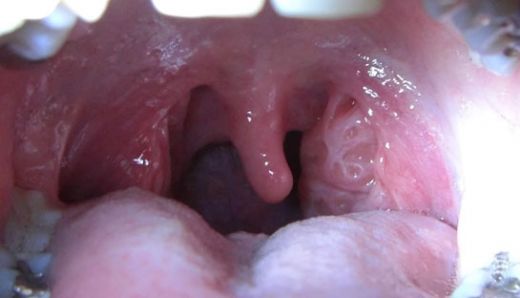

Bademcik Şişliği Nedenleri Bademcik şişliği, tıpta "tonsillitis" olarak bilinen bir durumdur ve genellikle bademciklerin iltihaplanması ile ilişkilidir. Bademcikler, boğazın arkasında bulunan iki küçük lenf düğümüdür ve vücudun bağışıklık sistemi için önemli bir rol oynar. Bu makalede, bademcik şişliğinin nedenleri, belirtileri ve tedavi yöntemleri üzerinde durulacaktır. Bademciklerin Yapısı ve Görevi Bademcikler, vücudun enfeksiyonlara karşı savunmasında kritik bir rol oynayan lenfoid dokudan oluşur. Özellikle çocuklarda daha belirgin olan bu yapılar, hava yoluyla veya ağız yoluyla vücuda giren patojenleri (bakteri, virüs vb.) tanıyarak bağışıklık tepkisini başlatırlar. Bademciklerin iltihaplanması, bağışıklık sisteminin bu patojenlerle savaşı sırasında meydana gelir. Bademcik Şişliğinin Nedenleri Bademcik şişliğinin birçok nedeni vardır. Bunlar arasında: